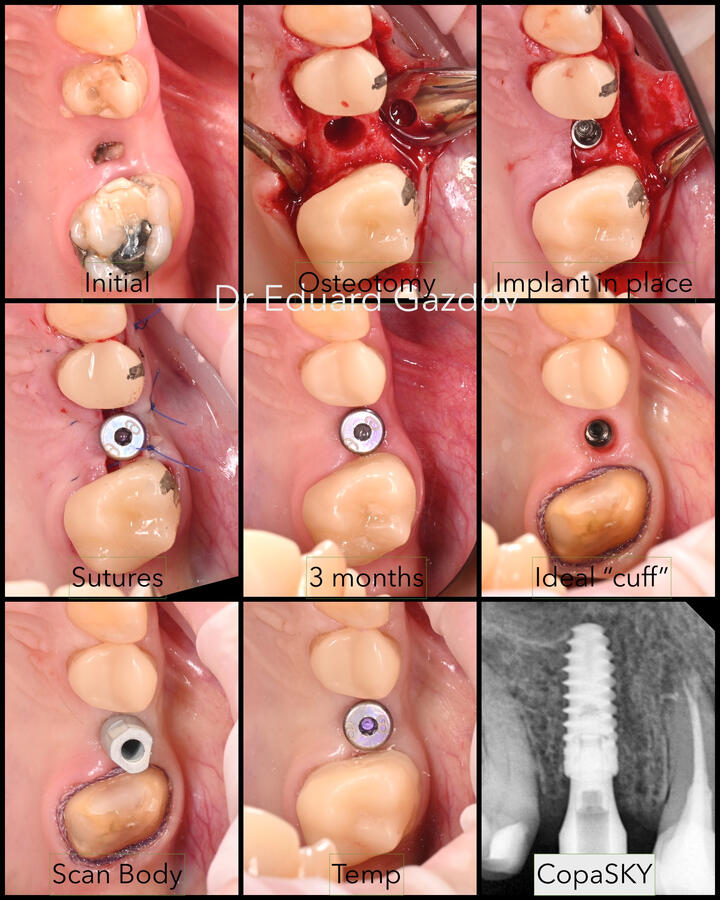

• Зъбни импланти

• Импланти с незабавно или водено поставяне – според случая и Вашите предпочитания• Фасети, корони и мостове с минимално изпиляване и естествена визия• Пълна трансформация на усмивката, планирани дигитално и изпълнени с внимание към естетиката• Хирургично вадене на зъби, включително трудни или инфектирани случаи• Директни фотополимерни възстановявания – бързо и щадящо решение при отчупвания и леки корекции• CEREC корони и инлеи, изработени и поставени на място, в рамките на часове• Прелекуване на стари канали, корони и мостовеРаботим под увеличение, използваме rubberdam, модерни дигитални технологии и най-висок клас материали.Обясняваме ясно какво правим и защо — за да се чувствате спокойни, уверени и информирани на всяка стъпка от лечението.